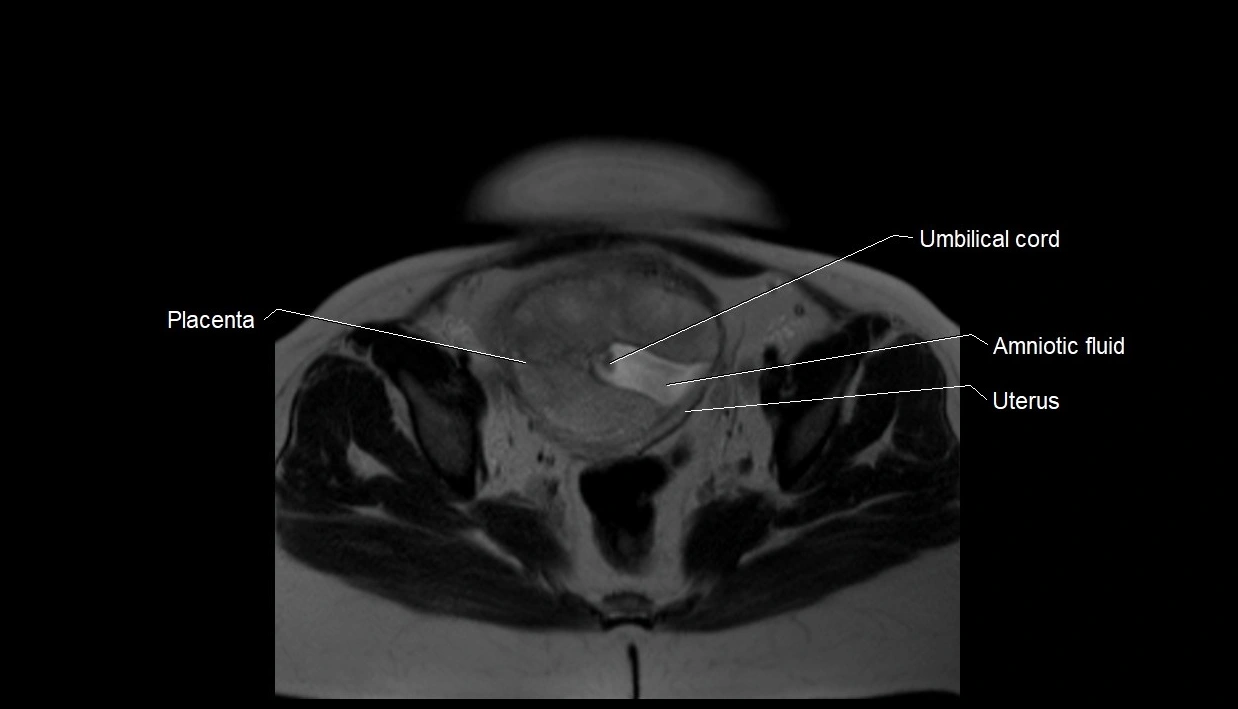

MRI Appearance

T2 HASTE (T2 GRE):

• Amniotic fluid shows very bright hyperintense signal

• Provides natural contrast against fetus and placenta

• Small particles (vernix) may appear as scattered hypointense foci within bright fluid

T1 GRE:

• Amniotic fluid shows low signal intensity (dark)

• Hemorrhage, infection, or proteinaceous content may cause focal or diffuse high signal intensity